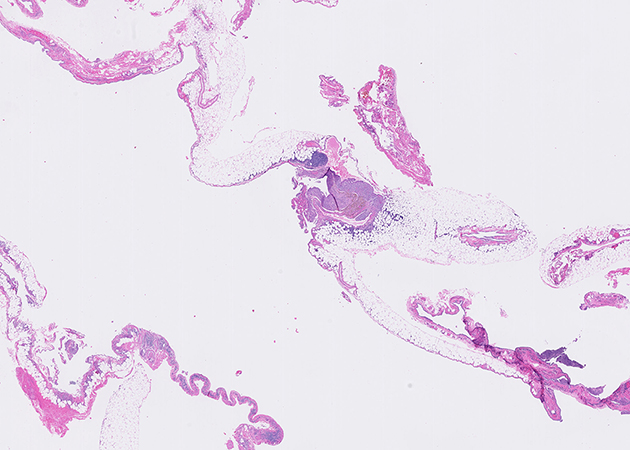

The submitted material consisted of fragments of lung parenchyma with firm consistency and poorly defined whitish-yellow areas. No evident tumor masses were identified. The intraoperative study (Figure 1) showed chronic suppurative inflammation with abundant infiltrate of neutrophils, lymphocytes, and plasma cells, associated with areas of necrosis and microabscesses. In the subsequent deferred study, rounded basophilic granules were identified, consisting of bacterial colonies with a central filamentous arrangement and a peripheral eosinophilic halo (Splendore-Hoeppli phenomenon) (Figures 2 and 3). Gram staining revealed Gram-positive filamentous bacilli (Figure 4). Grocott staining was positive (Figure 5), highlighting filamentous structures. Ziehl-Neelsen staining was negative (Figure 6).